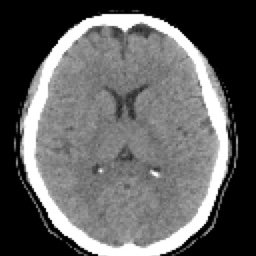

- RESUMEN TOMOGRAFIA

SIMPLE FINO (4) 129 images

HUESO FINO (5) 129 images

ARTERIAL FINO (7) 129 images

SIMPLE FINO COR (8) 91 images

SIMPLE FINO SAG (9) 75 images

ARTERIAL FINO COR (10) 90 images

ARTERIAL FINO SAG (11) 78 images

HUESO FINO COR (13) 90 images

HUESO FINO SAG (14) 75 images

HUESO FINO 3D (Creator:CT1) (100) 72 images